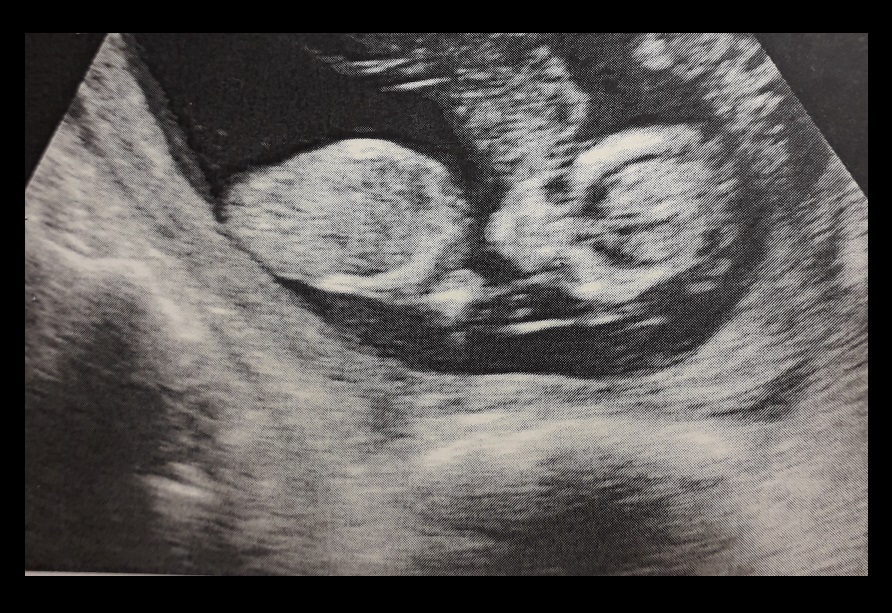

Semana 14 (segundo embarazo)

Llegamos a una de las semanas más deseadas del embarazo, la semana 14, que es la primera semana del cuarto mes y por ende la primera también del tan esperado segundo trimestre.